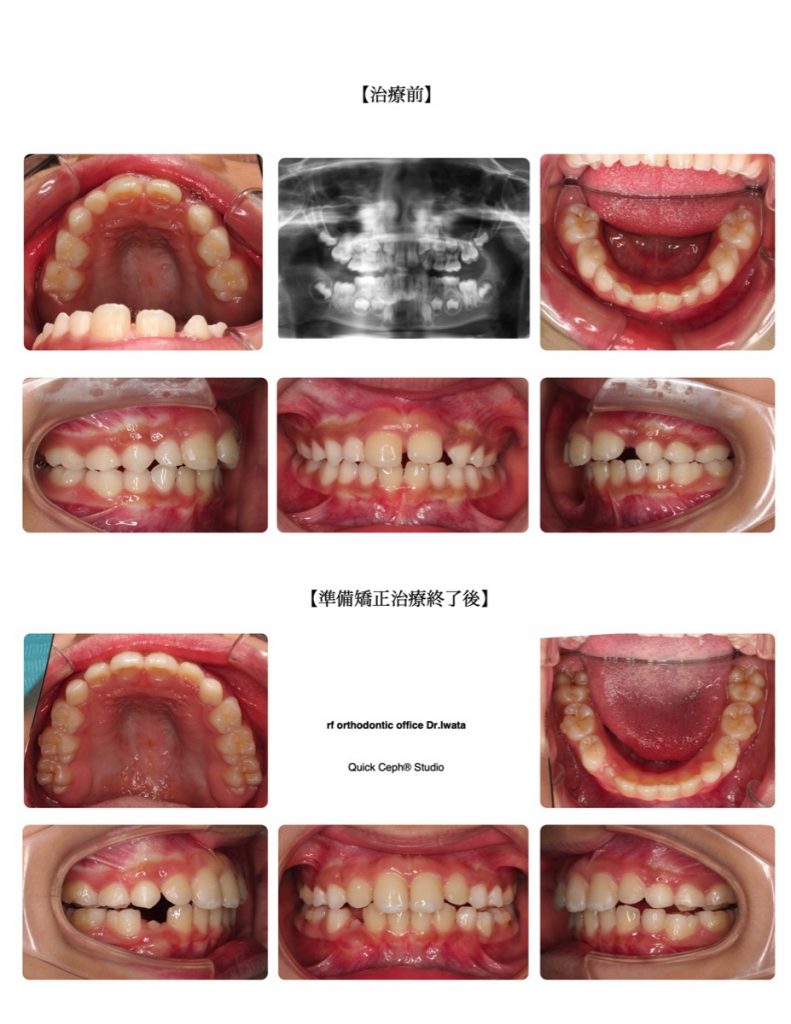

上顎前突症例 <永久歯の萌出スペース不足を伴う上顎前突に対する準備矯正治療>

「すきっ歯が気になる」「横の永久歯が出てくるスペースが足りない」「出っ歯で口が閉じづらい」といったお悩みを持つ方は少なくありません。特に、歯並びが不揃いな場合や前歯の隙間が大きくなっている場合、見た目だけでなく、噛み合わせにも影響が出ることがあります。このような症状に対して、矯正治療は非常に効果的です。今回は、上顎前突(出っ歯)や正中離開(すきっ歯)に関する治療方法と、それに伴うリスクについて詳しく解説します。

今回の主訴では、上顎前突と呼ばれる出っ歯の状態があり、口が閉じづらいという症状が見られました。出っ歯は、上顎の前歯が前方に出ている状態です。このような歯並びは、見た目に大きな影響を与え、口元が突出して見えることがあります。また、正中離開(すきっ歯)も併発しており、前歯の間に隙間が目立つことが特徴です。

これらの症状に対して、矯正治療ではスペース確保と歯列の調整が必要です。特に、横の永久歯が生えてくるためのスペースが不足している場合は、歯列拡大や場合によっては歯の間隔を調整する処置が行われます。出っ歯の改善には、上顎の歯を後ろに引くための力を加えることが重要です。矯正装置は今回はマウスピース型矯正を選択しました。

治療中は、歯と歯の間を調整し、歯が本来の位置に移動するように誘導します。正中離開や叢生に関しては、歯の隙間を埋めるためのスペースを確保し、より整った歯並びを目指します。